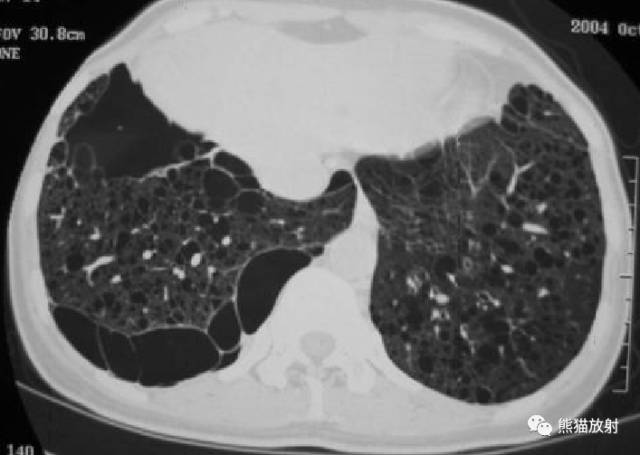

【影像表现】

胸部CT:双肺弥漫分布大小不等薄壁囊状空气密度影,且胸膜下区低密度影明显较其他部位大,周围见索条状高密度影。阴影之间肺组织基本正常。

②双肺弥漫分布囊状空气密度影,有薄壁,小叶中央动脉位于病灶边缘部分。此有别于小叶中央型肺气肿。

①小叶中央型肺气肿,见依据第二条。

②肺组织细胞增生症X(PLCH):分布以中上野为主,在显示囊状影的同时还可见多发结节。